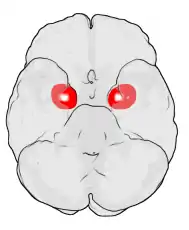

Amygdala

Location of the amygdalae in the human brain

The amygdala (/əˈmɪɡdələ/; pl.: amygdalae /əˈmɪɡdəli, -l/ or amygdalas; also corpus amygdaloideum; Latin from Greek, ἀμυγδαλή, amygdalē, 'almond', 'tonsil'[1]) is one of two almond-shaped clusters of nuclei located deep and medially within the temporal lobes of the brain's cerebrum in complex vertebrates, including humans.[2] Shown to perform a primary role in the processing of memory, decision making, and emotional responses (including fear, anxiety, and aggression), the amygdalae are considered part of the limbic system.[3] The term "amygdala" was first introduced by Karl Friedrich Burdach in 1822.[4]